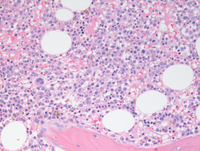

Bone marrow biopsy findings

Bone marrow biopsy demonstrated about 50-60% cellular marrow (otherwise almost normocellular for age) with evidence of an increased mononuclear blastic component percolating throughout the interstitium at higher power (image of the right side).

Bone marrow biopsy findings-higher power

Bone marrow biopsy at higher power demonstrates the mononuclear cells with evidence of dispersed chromatin compatible with blasts in the first two images. Paratrabecular clusters of blastic cells around the bone are also noted. The last image demonstrates a single dysplastic hypolobated megakaryocytes in the center of the field.